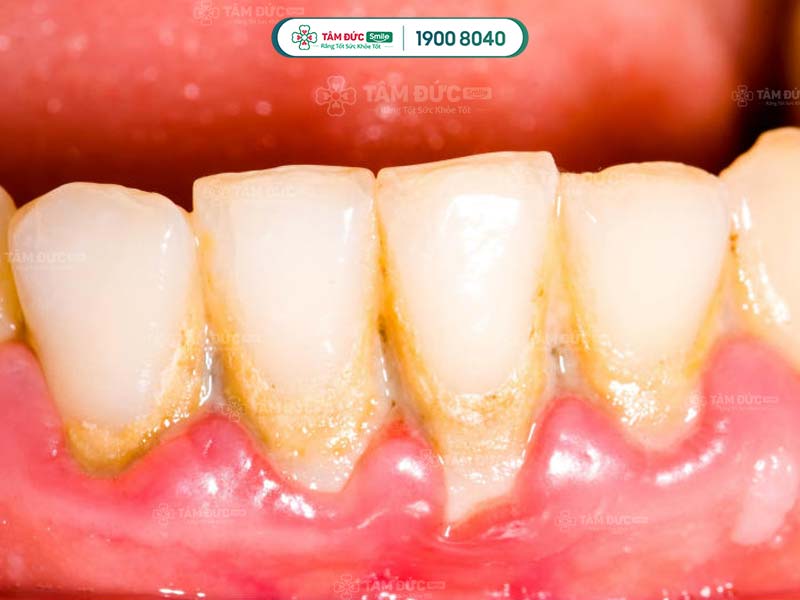

Cao răng có màu sẫm, tích tụ trên thân răng làm ảnh hưởng đến thẩm mỹ nụ cười. Cạo cao răng giúp Quý khách loại bỏ các mảng bám tối màu, trả lại hàm răng trắng sáng và đẹp mắt hơn.

Cao răng tích tụ lâu ngày sẽ gây ra các bệnh lý như: Sâu răng, viêm nướu, tụt nướu, mòn men răng, viêm nha chu,... Do đó, cạo cao răng thường xuyên giúp Quý khách ngăn chặn vi khuẩn phát triển, giảm nguy cơ mắc phải các bệnh lý răng miệng.

cạo cao răng để ngăn ngừa các bệnh răng miệng

cạo cao răng để ngăn ngừa sâu răng và viêm nhiễm